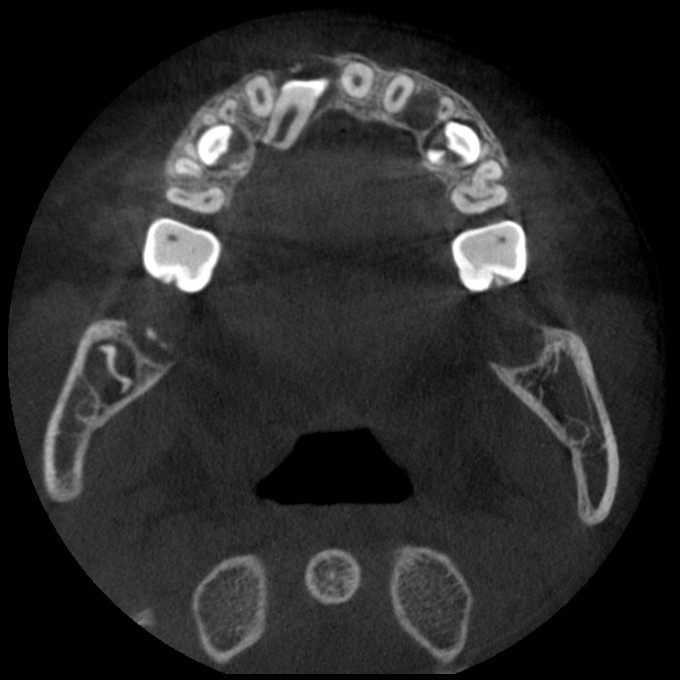

常规开展:数字化根尖片/横断牙合片、数字化口腔曲面体层片、头影测量侧位/正位片、手腕骨片、颅颌面CBCT、牙齿CBCT的检查以及涎腺造影、窦道 瘘管造影。

颅颌面CBCT

诊断范围涉及牙体牙髓病、牙周病、阻生牙/多生牙定位、种植牙术前CT评估分析、颞下颌关节CT诊断分析、,颌骨及涎腺疾病、颌面发育畸形、正畸治疗辅助诊断等大部分颌面部疾病,为临床医疗提供强有力的支持。